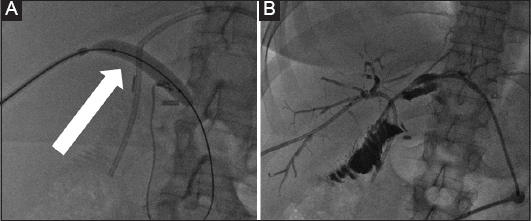

Figure 2 A 45-year-old female patient who developed benign biliary stenosis post laparoscopic cholecystectomy, with presence of stones. (A) Bilateral biliary drainage and dilation of the stenotic anastomosis with a high-pressure balloon (arrow). (B) Long-term drains with discoid end were left in situ for several months and the patient returned every 3 weeks for sequential dilation

thumblarge

Figure 3 A 48-year-old female patient with benign stenosis post biliodigestive anastomosis. (A) Initial drainage because of multiple small stones. (B) Cholangioscopic inspection to assess the presence of stones that were not visible in the cholangiogram. (C) Three months later, a new cholangiogram revealed the presence of a large stone (arrow). (D) The stone was retrieved with an extraction balloon. Presence of a “buddy-wire” to maintain access to the biliary tree

The success rates of balloon angioplasty for intrahepatic bile duct stone reach as high as 95.23% [11,41] of cases, with an average procedure duration of 65.8±5.3 min. On average, patients stayed in the hospital for 10.7±1.5 days. No instances of pancreatitis, gut issues, or perforations in the biliary duct were reported. Over a follow-up period of 2 years, there were no signs of reflux cholangitis or stone recurrence [11]. Comparing percutaneous transhepatic papillary balloon dilation (PTPBD) with ERCP, the PTPBD technique had a success rate of 99% compared to 98% for the ERCP technique (relative risk 1.02, 95%CI 0.91-1.08; P=0.12). Complication rates were lower for PTPBD at 4% (13 of 360) versus ERCP at 8% (13 out of 171) (relative risk 0.27, 95%CI 0.12-0.61; P<0.001). The PTPBD procedure took more time under fluoroscopy and resulted in greater radiation exposure, with an average difference of 28.7 min (95%CI 22.2-35.2) and 384.3 mGy (95%CI 296.5-472). When matched groups were compared using a propensity score analysis, PTPBD displayed a marginally better success rate and notably fewer complications [42] (Table 1).